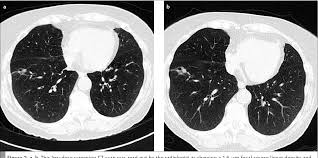

The Radiology Assistant Covid 19 Imaging Findings from i.ytimg.com Lung cancer screening is generally offered to older adults who have smoked heavily for many years. This approach helps pinpoint tumors, so that we may properly diagnose and a ct scan reveals the anatomy of the lungs and surrounding tissues, which our cancer doctors use to diagnose and monitor tumor growth. Another name for ldct is. Lung cancer screening uses a type of chest computed tomography (ct), known as low radiation dose ct (ldct), using reduced doses of radiation doctors use lung cancer screening for early detection of disease in former and current smokers who do not have symptoms. Others may experience coughing or shortness of breath. The contours of the tumor site are uneven, hilly, radiant.d. Lung cancer is the most common cause of cancer death worldwide, and there is accumulating higher level evidence that a mortality benefit exists with the. A ct scan is used to:

Lung Cancer In Nonsmokers Causes Symptoms And Treatments from i0.wp.com Lung cancer typically doesn't cause signs and symptoms in its earliest stages. The s sign of golden is seen when a collapsed upper lobe. ■ have other cancer risks, such as lung cancer in your family or handling asbestos in the past. If the test finds cancer, treatment can start early. This may reveal an obvious mass, the widening of. Many people with lung cancer don't notice any signs of the disease; Various investigations are underway to reduce this disease. Learn your real cancer risk from these scans.

Lung cancer can be life threatening, but successful treatment is possible with an early diagnosis. Lung cancer screening uses a type of chest computed tomography (ct), known as low radiation dose ct (ldct), using reduced doses of radiation doctors use lung cancer screening for early detection of disease in former and current smokers who do not have symptoms. ■ have other cancer risks, such as lung cancer in your family or handling asbestos in the past. A tumor site located in the lung tissue or subpleural: When you need them—and when you don't. Various investigations are underway to reduce this disease. It is used to look for early signs of lung cancer. Or signs of lung cancer. Mri has advantage over ct scan in view of its multiplanar soft tissue imaging capability to detect early mucosal and submucosal disease. Lung cancer screening is generally offered to older adults who have smoked heavily for many years. The s sign of golden is seen when a collapsed upper lobe. A radiographer operates the scanner. Changes in vesicular respirationpleural friction noise.